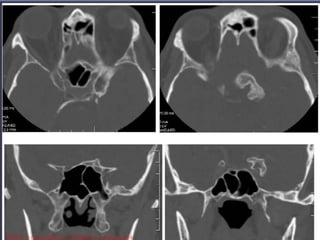

Sphenoid sinus

• SCCA

• Chordoma

• Sarcoma

• Metastasis

• Inflammation: sinusitis